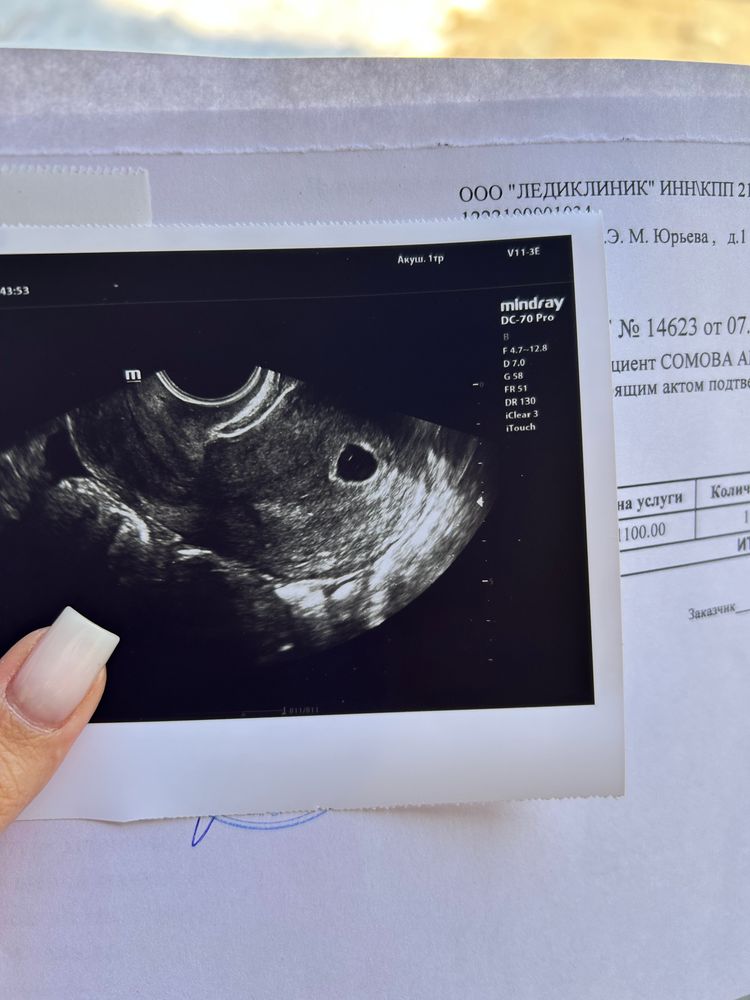

6 недель по мес, 5 недель по узи

У вас пя 12 мм почти,это не 5 недель,а 5,5 недель,а вообще все врачи заметила с одним размером пя разный срок ставят,у меня пя 8 мм с жм тоже 5 недель,здесь вот для примера пя 9 мм и срок 5,5 соответствует,а у вас пя больше,а срок меньше,короче не забивайте голову сроками у вас все соответствует,более точный срок по размеру эмбриона,а не по пя,пя как раз разное может быть и роли в сроке не играет Изображение

У меня тоже 6 недель, по узи позавчера было 5 недель и 1 день (разница 4 дня). Сейчас смотрю на снимок узи, у вас 1 белая точка, а у меня почему-то 2 таких... интересно, что это? Я была в таком шоке, что даже не спросила)